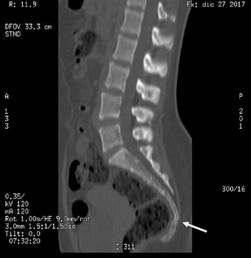

One week later, the patient returned to the emergency department reporting intense pain (10 points on the pain scale) in the lumbosacral region associated with difficulty to sit. On physical examination, she presented edema, pain and decreased mobility of the arches. The woman was assessed by neurosurgery, which ordered lumbosacral spine tomography and lumbosacral spine nuclear magnetic resonance imaging (LSN-MRI), reaching a diagnosis of sacrococcygeal dislocation (Figure 1). She was discharged with orders for outpatient treatment with acetaminophen 500mg every 6 hours, diclofenac 100mg per day, and pregabalin 50mg every 12 hours, and instructions to sit on a flotation cushion.

Lumbosacral spine CT showing sacrococcygeal dislocation.

Figure 1: Lumbosacral spine CT showing sacrococcygeal dislocation.

Source: Document obtained during the study.